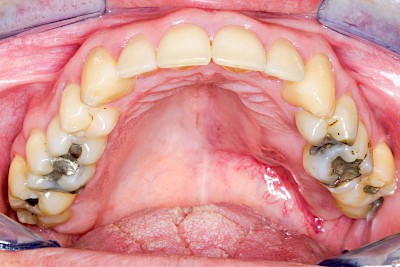

Schwellung ohne Eiter: kugelförmig

Demgegenüber entstehen Auftreibungen der Weichgewebe in Folge mechanischer Dauerreize (Reizfibrom) langsam über Wochen, Monate oder Jahre. Auch Gewohnheiten (Wangensaugen, Lippenbeißen) mit geringem Druck können als Dauerreiz in der Folge zu einer Wucherung der Weichgewebe führen. Fibrome werden nicht selten auch beobachtet in der Nähe einzelner fehlender Zähne – die Lippen oder Wangen beginnen dann, diesen Raum "aufzufüllen" (Vakatwucherung). Reizfibrome sind meist "kugelartig".